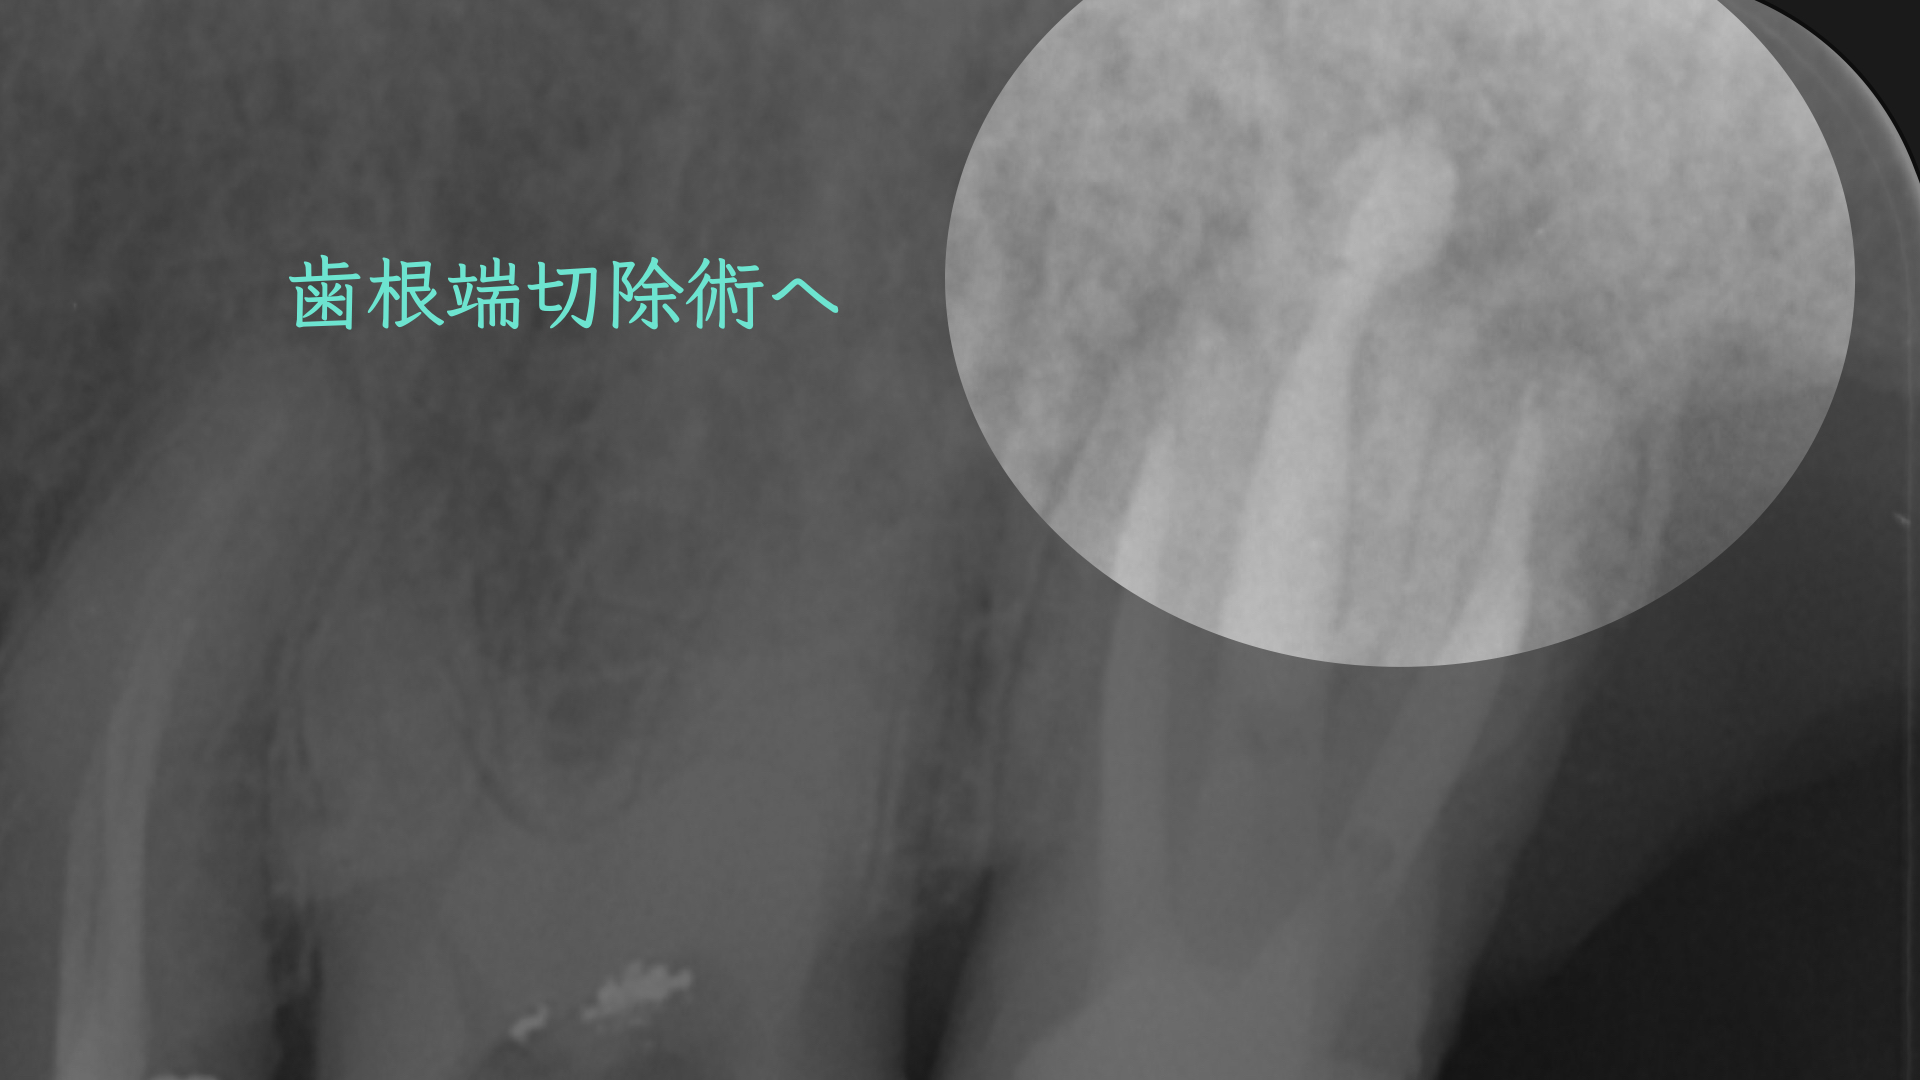

教科書によると、この部位は適応症でなく、一般的には意図的再植の適応症にはなりますが、このような歯根が離開している歯を一度抜歯するのは破折のリスクがあります。

適応症ではないのは大口蓋動脈の存在です。

論文より今回のケースは安全であると判断し、歯根端切除で対応しました。

切断した歯根です。表面が粗造になっており、感染が根尖孔外にあったことを認めます。

注意しておこないました。